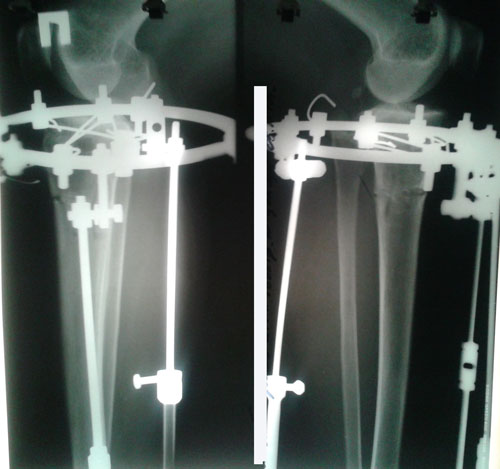

Исходник - 34 года.

Дата операции 20.10.2016г.

Дата снятия аппаратов 19.01.2017г.

Срок лечения 90 дней.